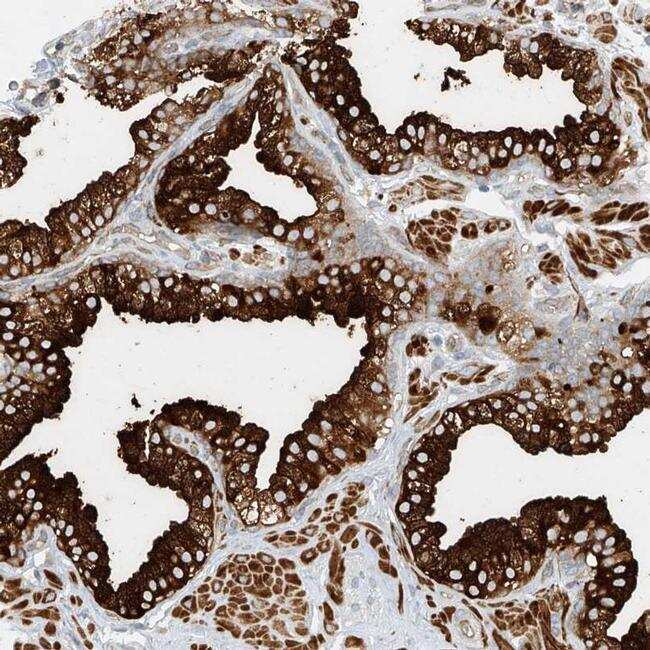

- Immunohistochemical analysis of LYRM9 in human prostate using LYRM9 Polyclonal Antibody (Product # PA5-54678) shows strong cytoplasmic positivity in glandular cells.